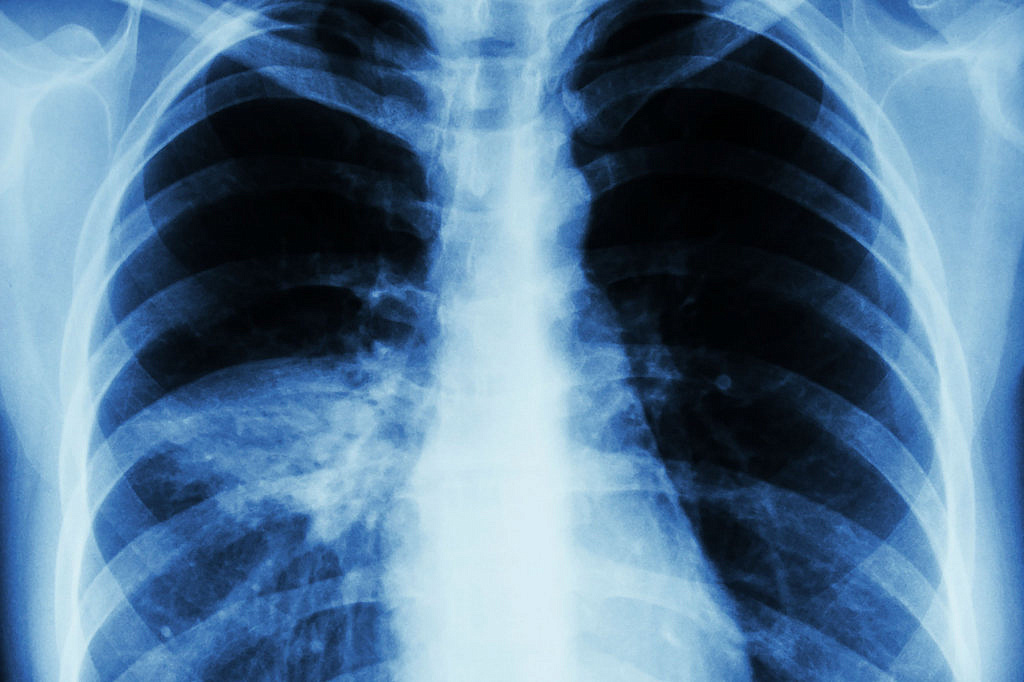

Показатели по заболеваемости коронавирусом за неделю снизились на треть. По ОРВИ зарегистрировано на 560 случаев меньше, чем в предыдущие 7 дней. При этом заболеваемость внебольничными пневмониями в регионе остается на высоком уровне.

Сегодня показатель заболеваемости внебольничными пневмониями на 66,47% превышает среднемноголетний, сообщает амурское управление Роспотребнадзора.